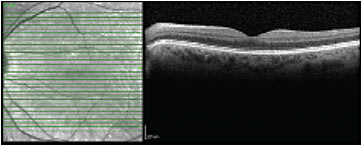

Case 3: A 64-year-old female with minimal cataract has been complaining of a prominent floater in the left eye for 2 years. This caused her difficulty with reading and driving despite her 20/20 measured acuity. She already had a posterior vitreous detachment and stated that the floater “never seems to move out of the way” (Figure 3). Video SLO confirmed this, as it is often the case that patient descriptions of their floaters exactly match video SLO findings (Video 4). She was offered surgery, which she underwent, and she was happy with the outcome. Follow-up SLO imaging shows absence of any shadowing (Figure 4).